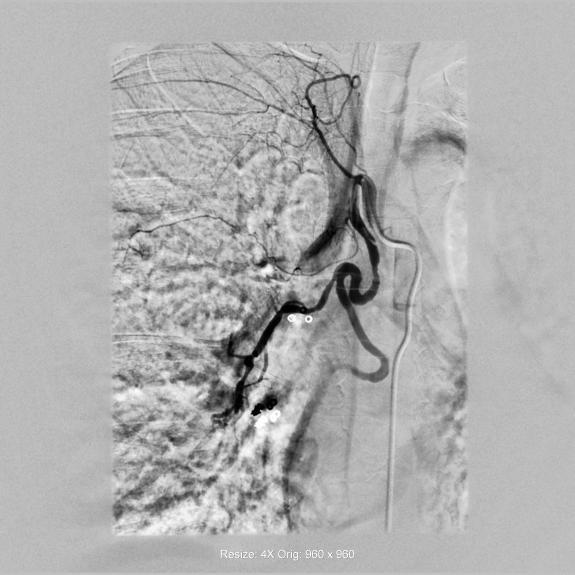

术后造影(R)

“能不能少遭点罪?”面对家属的恳求,医院介入导管室医护团队决定启用新技术。通过术前CTA与术中DSA影像精准配准,借助3D Fusion技术让迂曲血管立体呈现,再利用Overlay技术将血管走形叠加在实时画面上,原本难以定位的出血点被“一眼锁定”。微导管在导航引导下快速精准到达靶血管,注入栓塞剂后成功止血。从麻醉到手术结束,全程仅用45分钟,较传统手术缩短近2小时。

术后,冯阿姨未出现射线剂量过量、造影剂损伤、脊髓动脉误栓等风险。因手术中减少了导管、导丝等耗材的使用,此次治疗费用较传统手术降低约20%。“本来还怕又花钱又遭罪,没想到这么省心。”康复后的冯阿姨感慨,好技术能帮患者少受苦。这场手术不仅实现了从“经验盲探”到“数字精准”的技术变革,更体现了医院以患者为中心的服务温度,为咯血患者撑起了生命保护伞。